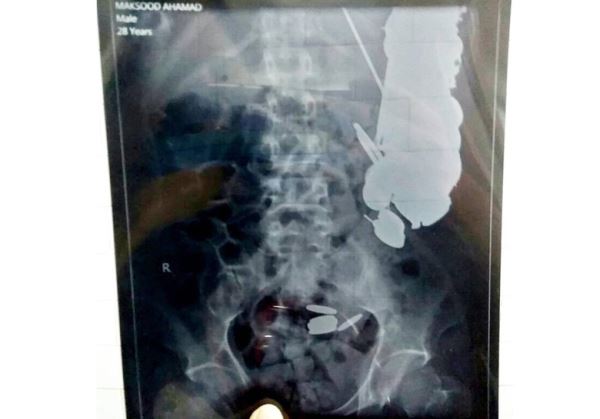

Сначала у него предполагалось пищевое отравление, но потом после эндоскопа, а потом рентгеновского снимка внутри мужчины в желудке и кишечном тракте увидели множество инородных тел.

Хана сразу же отправили на операцию и хирурги извлекли из него 263 монет, 100 гвоздей и множество других металлических вещей.

Одни только гвозди весили полтора килограмма, а все вместе с монетами, гвоздями, кусками стекла, бритвенными лезвиями и большим куском ржавого железа весило внушительные 7 килограммов.